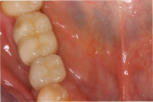

Durch Transplantate kann verlorenes Gewebe wieder aufgebaut werden. Damit wird eine dauerhafte Stabilität der Gewebe und damit auch des Knochens erzielt und eine gute Putzfähigkeit für Zähne oder Implantate erreicht. Beispiele:

Mikrochirurgischer Wundverschluss

Gingivatransplantat fixiert

Zustand 3 Wochen post OP